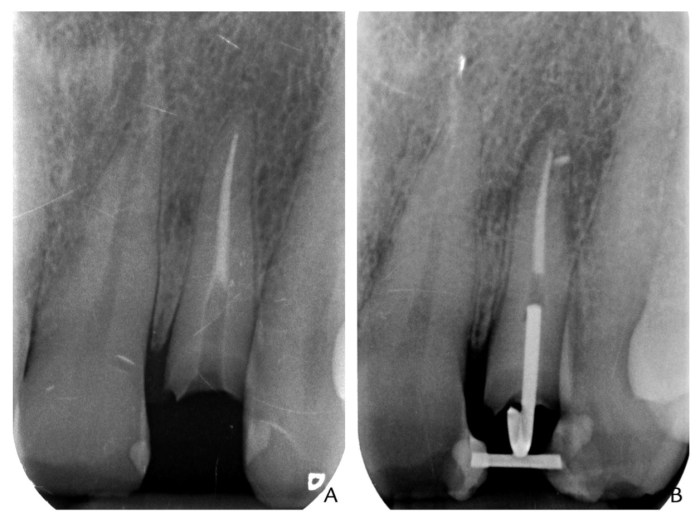

使用鄰牙來做orthodontic extrusion的case report—Re(2016) 2016 年 11 月 07 日2016 年 11 月 09 日 yehhsinchi 診斷、固定式假牙診斷、固定式假牙 jpd-2016-vol-116-p-464-466 在前牙有時候可能會遇到這樣的情形,就是之前做的單顆假牙斷了然後subgingiva,但是牙根還不錯,想要做局部矯正拉出來,這個case report是利用兩側的鄰牙去拉,在某些情形下可是使用看看。 分享此文: 分享到 X(在新視窗中開啟) X 分享到 Facebook(在新視窗中開啟) Facebook 喜歡 正在載入...